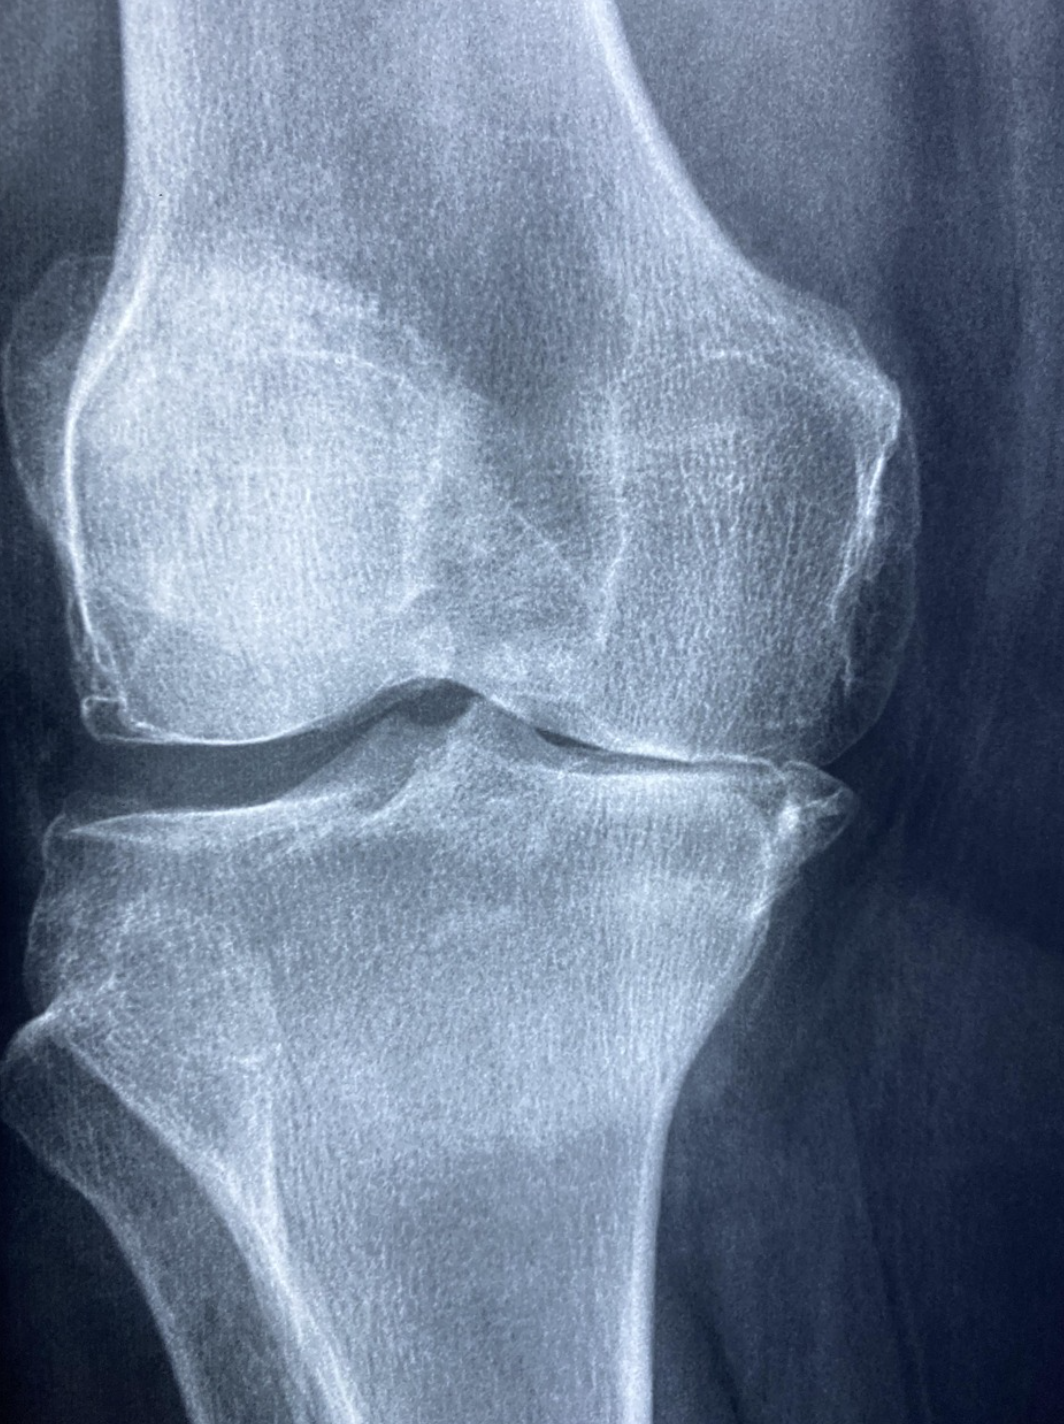

고관절 인공관절 치환 수술은 크게 사전 검사, 마취, 절개 및 인공관절 삽입, 봉합의 단계로 이루어집니다. 먼저 수술 전 정밀 검사를 통해 골밀도, 혈액검사, 심폐 기능을 평가하고, 환자의 전반적인 건강 상태를 확인합니다. 이 과정에서는 영상의학검사(CT·MRI)와 골밀도 검사, 심전도·흉부 X-ray 등이 시행되며, 서울아산병원과 삼성서울병원 등 주요 의료기관에서는 환자 맞춤형 3D 모형을 활용해 시뮬레이션을 진행하기도 합니다. 마취는 전신마취 또는 척추마취 중 환자 상태와 수술 방법에 따라 선택하며, 척추마취를 통해 수술 후 초기 통증을 줄이는 병원도 늘어나는 추세입니다. 마취가 완료되면 외측 혹은 전측 접근법을 통해 약 8~10cm의 절개를 시행하고, 손상된 관절을 절제한 뒤 인공관절(금속·초고분자합성체)로 교체합니다. 일부 병원, 예컨대 세브란스병원에서는 최소침습 절개 및 로봇 보조 수술 장비를 도입해 절개를 최소화하고 회복 속도를 높이고 있습니다. 인공관절 삽입 후에는 관절의 안정성과 다리 길이 균형을 확인한 뒤 봉합과 드레인 삽입으로 수술을 마무리합니다. 전체 수술 시간은 1시간 30분에서 2시간 이내가 일반적이며, 수술 직후 중환자실이 아닌 회복실에서 관찰하며 환자 상태를 체크하는 것이 특징입니다. 수술 후 1~2일 차에는 조기 보행을 권장하며, 각 병원별 전문 재활팀이 환자별 통증 관리와 이동 보조 기구 사용법 등을 교육합니다. 이를 통해 합병증 발생률을 낮추고 빠른 일상복귀를 지원합니다. 이처럼 서울의 주요 의료기관은 고도의 수술 기법과 첨단 장비, 전문 팀을 바탕으로 안전하고 정확한 고관절 인공관절 치환 수술을 제공합니다.

인공관절 치환 수술 후 발생할 수 있는 주요 합병증에는 감염, 관절 탈구, 심부정맥혈전증(DVT), 다리길이 부조화, 신경 손상 등이 있습니다. 가장 심각한 감염은 수술 부위에 국한된 국소 감염부터 전신 패혈증으로 이어질 수 있어, 서울아산병원 감염관리팀과 같은 전문 부서에서는 항생제 예방적 투여와 수술 중 철저한 멸균 관리를 시행합니다. 관절 탈구는 주로 수술 직후 초기 보행 시 발생할 수 있으며, 이를 예방하기 위해 수술 방식에 따라 금기 자세(과도한 굴곡·내전·내회전)를 숙지하고, 보행 훈련 초기 단계에서 보조기구를 사용하는 것이 중요합니다. 심부정맥혈전증은 하지 및 골반 정맥 내 혈전이 형성되어 폐색전증으로 진행될 위험이 있어, 수술 후 조기 보행과 더불어 압박 스타킹 착용, 케톤산제 또는 저분자 헤파린 투여 등으로 예방합니다. 다리길이 부조화는 인공관절 삽입 위치와 각도 차이로 두 다리 길이가 달라지는 현상으로, 수술 전 3D 모의 수술 계획과 수술 중 정밀 계측을 통해 최소화하며, 부조화가 발생하면 깔창 조정이나 보조 기구 등을 통해 보정할 수 있습니다. 드문 경우지만 주변 신경(대퇴신경, 좌골신경) 손상이 발생할 수 있어, 통증·감각 이상 증상이 지속되면 신경학적 검사를 통해 조기에 대응해야 합니다. 또한 만성 통증 및 가동 범위 제한이 나타날 수 있으며, 이 경우 관절 내 스테로이드 주사나 추가 물리치료, 필요 시 추가 수술을 고려해야 합니다. 합병증 발생률은 병원의 경험, 환자 개별 건강 상태에 따라 달라지므로, 삼성서울병원·세브란스병원 등 풍부한 수술 경험을 가진 전문 의료기관을 선택하는 것이 안전합니다. 수술 전후 환자 교육, 정기 검진, 재활 모니터링을 통해 합병증을 최소화하고, 이상 징후 발생 시 신속한 진단과 치료가 중요합니다.